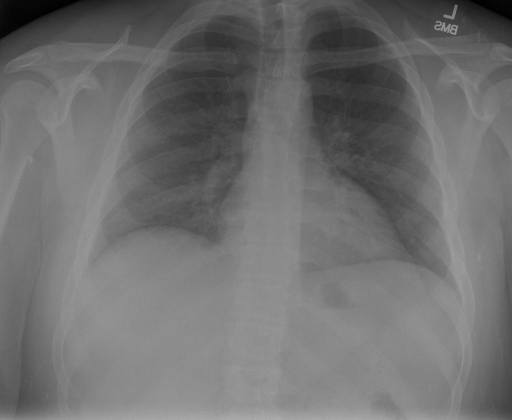

|X光影像|诊疗报告(医生)|XrayGLM|

|:-|:-|:-|

||X光图片显示没有扭曲的区域、可疑的骨质不透明度或胸腺积液。心脏大小轻微增大,但非常稳定。此外,没有气胸的证据,肺野也正常。总体来说,X光片显示没有急性心脏异常,但要注意轻微的心脏扩大。|X光片显示,心脏大小正常。肺部和纵隔轮廓清晰,没有气胸或胸腔积液的证据。骨骼结构完整,没有任何急性异常。|